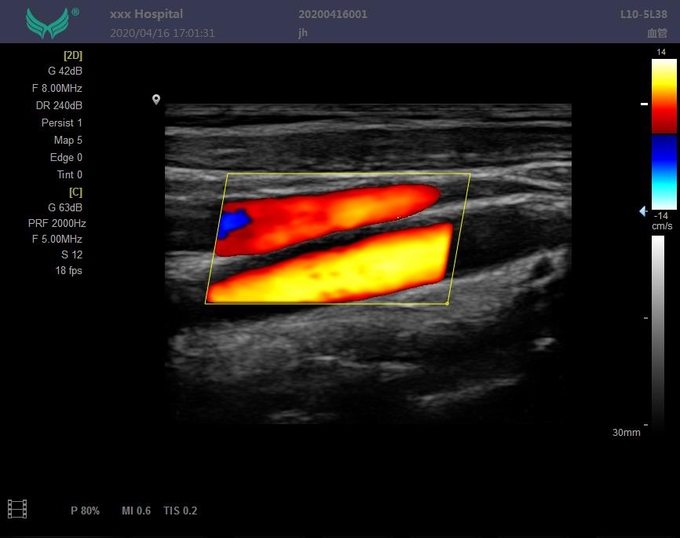

--Режим работы монитора: B, B/B, m, B/M, CFM, CMF/B, PDI, B/PW, CW и другие режимы;